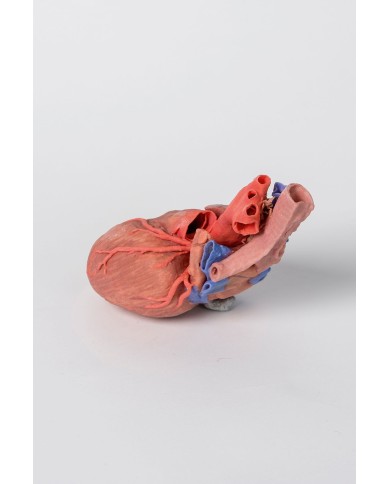

Modello anatomico di cuore, ingrandito 2 volte, su cavalletto

Questo modello dettagliato mostra, oltre alle strutture anatomiche del cuore, anche una parte del diaframma (base)

Realizzato in stampa 3D ad elevatissima risoluzione a colori.